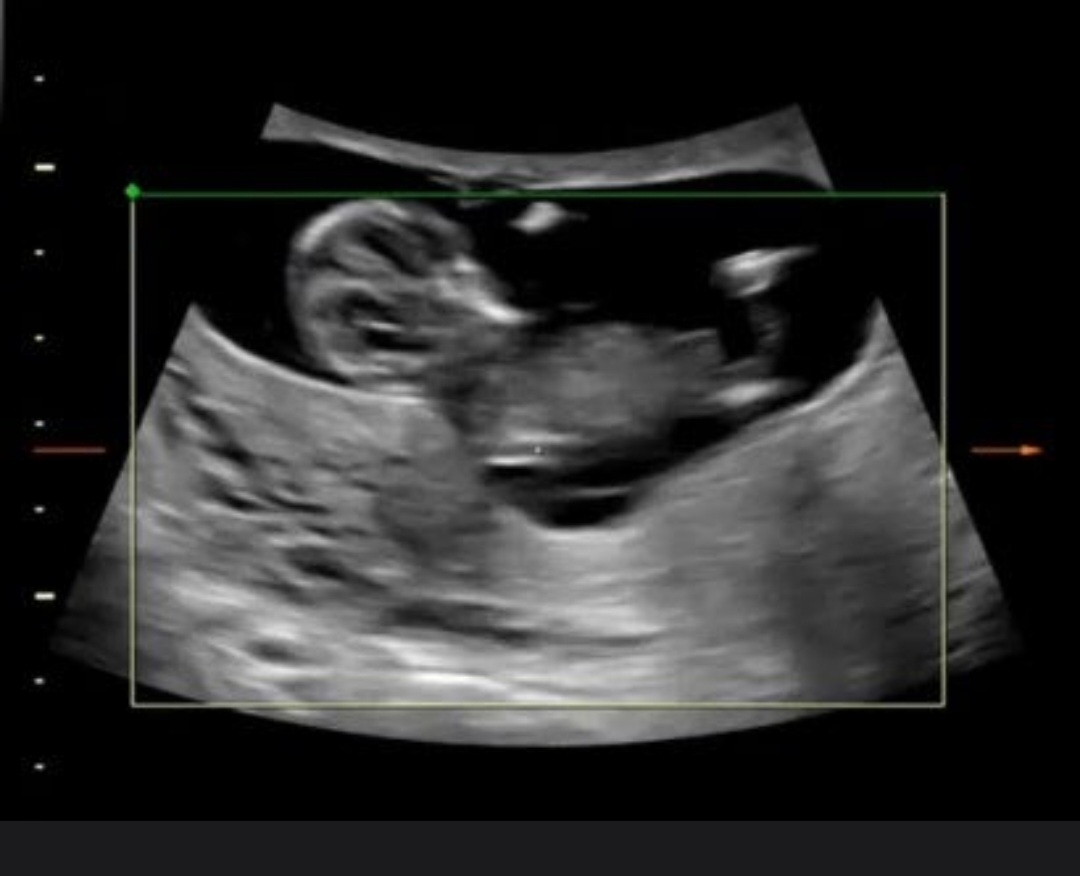

12주 각도법!

딸 아들 너무갈려서ㅜㅜ 많은 참견부탁드립니다